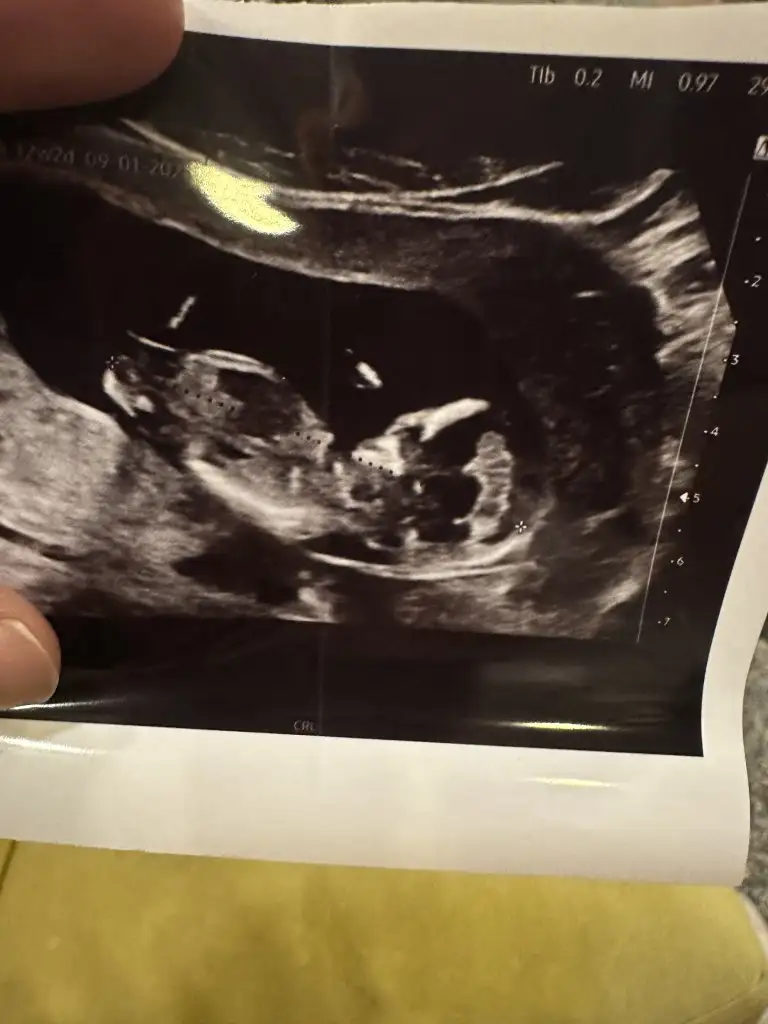

Bence net kızBanada bakın yaaa![]()

Nerden belli oluyorBence net kız![]()

Teşekkür ederim canımBence net kız![]()